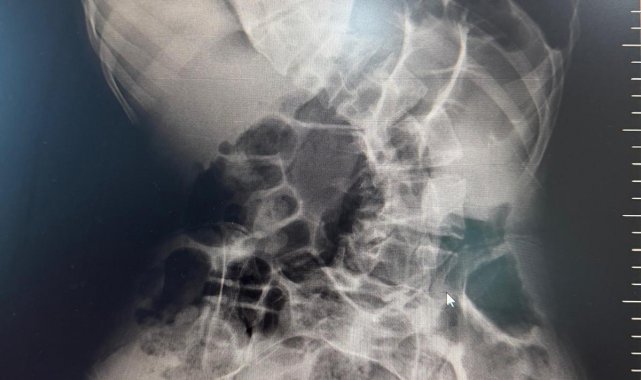

Başarılı geçen ameliyat sonrası hastanın yaşam kalitesinin önemli ölçüde arttığını belirten Ortopedi ve Travmatoloji uzmanı Prof. Dr. Mehmet Atıf Erol Aksekili, skolyoz hakkında bilgi vererek, "Skolyoz kısaca omurganın S şeklini almasıdır. Ön-arka planda omurganın S şeklini almasını biz kısaca skolyoz diyoruz. Skolyoz en sık adolesan dediğimiz ergenlik döneminde görülür. Ancak diğer hastalıklarla birlikte görüldüğünde daha ileri seviyelerde karşımıza çıkabilir. Hastamız 18 yaşında bize başvurdu. Nöromüsküler skolyoz dediğimiz, nörolojik hastalıkların eşlik ettiği bir skolyoz tipi mevcut. Bu skolyozlar erken yaşta ortaya çıkar ve daha hızlı ilerler. Bu yüzden hastamız bize 90 dereceden daha ileri bir seviyede başvurdu" dedi.

Erken teşhis edilmesi halinde daha az cerrahi ile daha iyi sonuç alınabileceğini belirten Aksekili, "Skolyoz erken tanındığında fizik tedavi, egzersiz ve korseleme gibi yöntemlerle ilerlemesini kontrol altına alabiliyoruz. Hastamızda ileri skolyoz olduğu için iki aşamalı cerrahi uygulandı. İlk aşamada Halo Femoral traksiyon yöntemiyle skolyoz kısmen düzeltildi. İkinci aşamada ise vidalar, rodlar ve osteotomi ile omurga düzeltildi" diye konuştu.